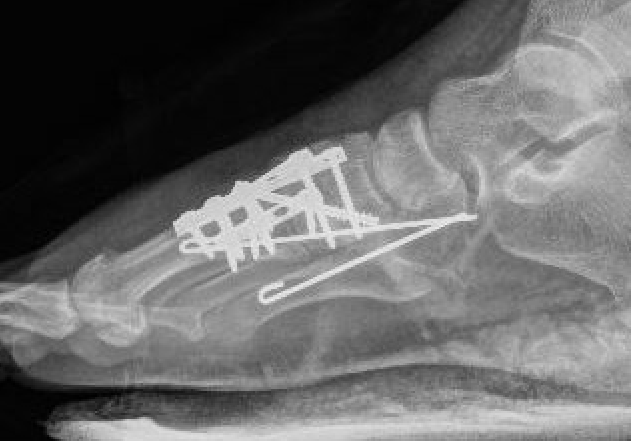

1st, 2nd & 3rd TMT joints

- trans-articular screw fixation

- bridge plate fixation

- primary arthrodesis

4th & 5th TMT joints

- consider K wire fixation

Screw fixation 1st and 2nd TMT with K wire fixation 3rd / 4th / 5th

Bridge plating of 1st, 2nd, 3rd & 4th TMT with screw fixation of Lisfranc joint

Fusion of 1st TMT, plating of 2nd and 3rd TMT, K wire stabilization of 4th and 5th TMT